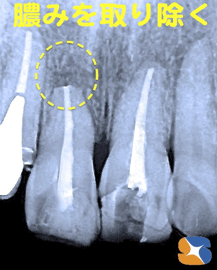

治療開始から3ヶ月。まだ1本、グラグラと膿みの排出が続く。急遽、根の先の膿んだ部分を手術を行って取り除く。手術後の経過は良好、グラつきも止まる。よし!〜あとひと踏ん張り。